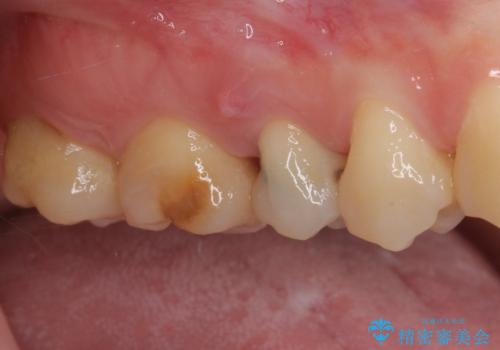

神経が死んで変色した歯 根管治療とオールセラミッククラウン

- 近医にて右上奥歯に大きなむし歯があると指摘されたとのことで来院された患者様です。

診査の結果、既に歯の神経は失活して変色しておりましたが、特に痛みは認めませんでした。

根管治療を行った後にオールセラミッククラウンにて補綴することとしました。